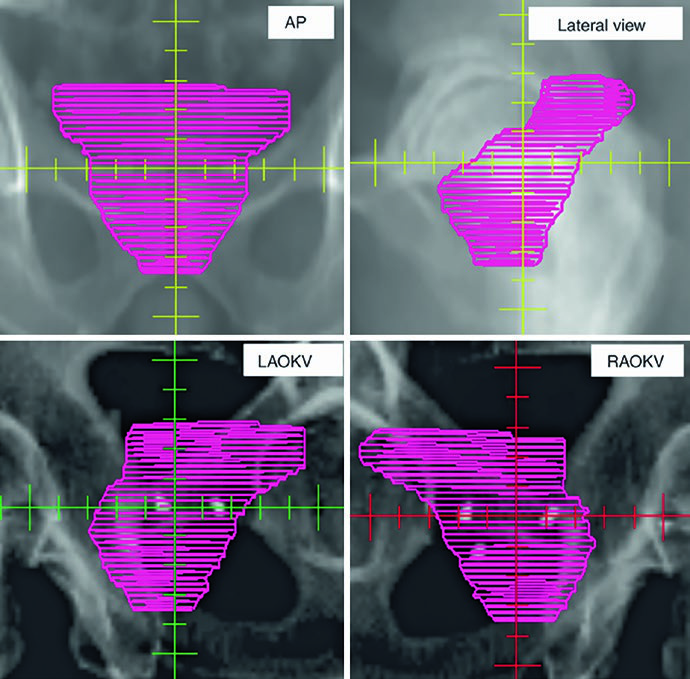

As figuras ajudam a entender por que o capítulo insiste na checagem 3D. A Fig. 25.1 mostra a sequência axial de um planejamento definitivo com TC de 2 mm fundida à RM T2, começando nas vesículas seminais e descendo até o ápice. A legenda chama atenção para o espaçador retal de hidrogel, melhor visto na RM T2, e cita o trabalho de Atluri sobre o uso de contraste iodado para facilitar a delimitação do espaçador mesmo sem apoio de RM. Já a Fig. 25.2 projeta o CTV em vistas AP, lateral e oblíquas. Ali fica claro o formato globular da glândula sob uma estrutura superior alada correspondente às vesículas seminais. Se o contorno avançar demais para o diafragma urogenital, a projeção inferior denuncia o erro rapidamente.

Outro detalhe importante da projeção tridimensional é a detecção de irregularidades slice a slice. O texto observa que correções exageradas entre cortes podem gerar um volume artificial, pouco fiel à anatomia, especialmente quando se tenta compensar deformação orgânica e movimento médio ao longo do tratamento. É um comentário curto, mas muito útil. Em próstata, boa parte dos erros não nasce de um corte catastrófico. Nasce de pequenas incoerências repetidas em muitos cortes.